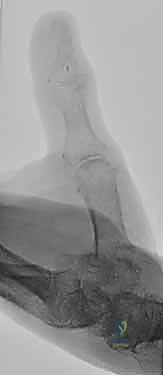

1. بتر الإبهام: الإبهام يمثل نصف وظيفة اليد، وإعادة زرعه تعتبر أولوية قصوى مهما كان مستوى البتر.

يعتبر الفهم الشامل لتشريح الأصابع، بدءاً من مفصل السلاميات السنعية (MCP) وصولاً إلى طرف الإصبع (Distal Phalanx)، أمراً بالغ الأهمية. يختلف الإبهام في سماته التشريحية الفريدة مقارنة بالأصابع الأخرى، حيث يمتلك سلاميتين فقط ولكنه مسؤول عن 40% إلى 50% من وظيفة اليد الإجمالية.